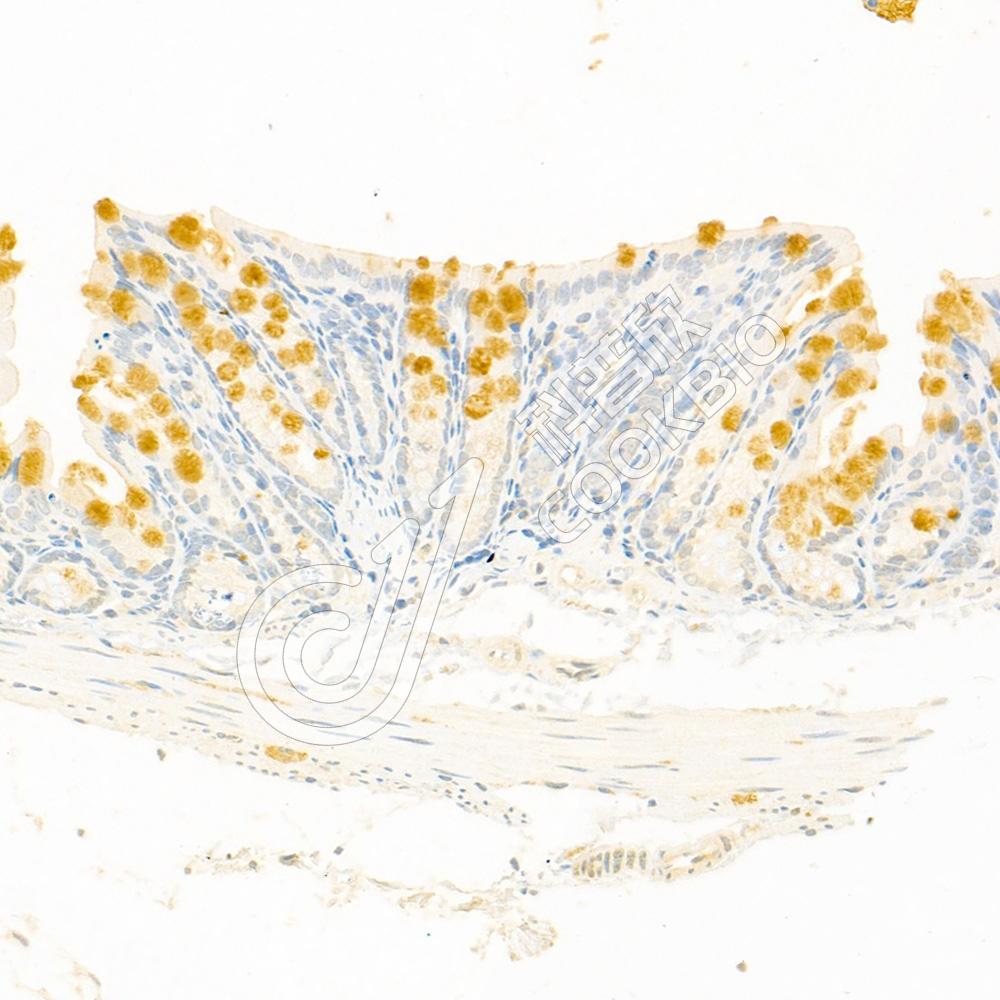

IHC检测ClC-5蛋白(货号 K1337161).

样品: 人肾, 4%多聚甲醛 (货号KSG1101) 固定12-24小时.

抗原修复: 柠檬酸抗原修复液(干粉, pH 6.0) (KSG1201), 98℃, 20分钟.

—抗: 1: 300稀释, 4℃ 孵育过夜.

二抗: S-vision免疫组化多聚二抗(山羊抗兔),即用型 (货号KB3906), 室温孵育20分钟.

样品: 小鼠肾, 4%多聚甲醛 (货号KSG1101) 固定12-24小时.

样品: 大鼠肾, 4%多聚甲醛 (货号KSG1101) 固定12-24小时.